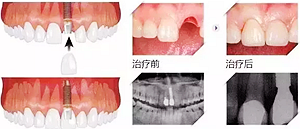

7、大幾千甚至過萬的種植牙

當(dāng)牙齒最終齲壞到只剩殘根,只能拔除,拔牙雖然不貴,但是拔牙之后的鑲牙并不便宜,目前比較好的鑲牙方式種植牙,一般要大幾千甚至過萬元一顆。這個(gè)價(jià)格對(duì)于普通人來說算很貴了。但沒辦法,誰叫你一拖再拖呢,快趁有人工補(bǔ)救的機(jī)會(huì)種上吧,有些人想種牙還受身體條件限制種不了呢。